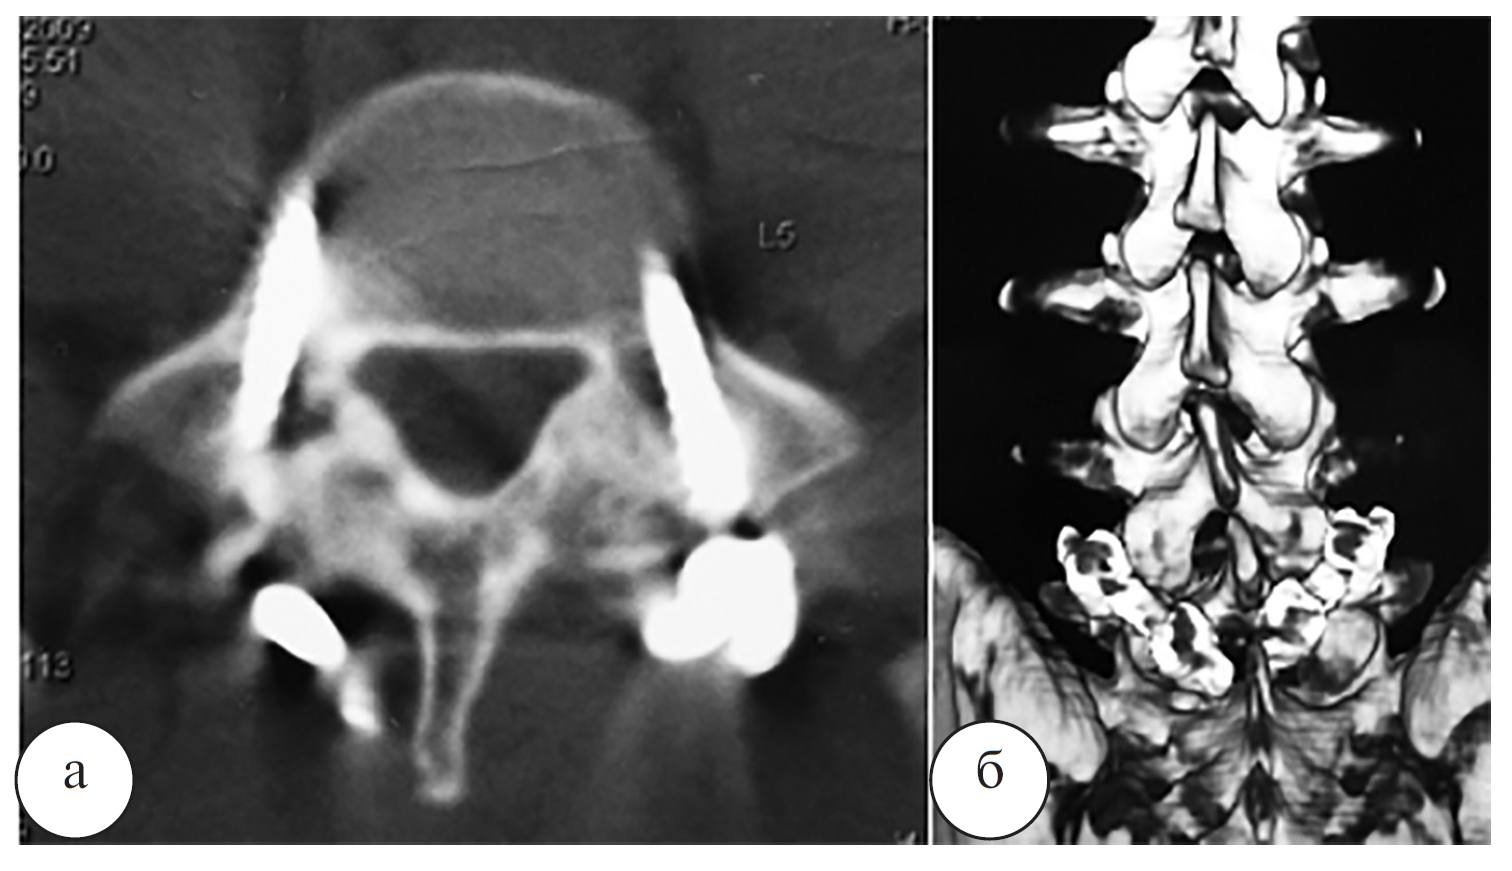

Рис. 2. Рентгенограмма (а) и МР-томограмма (б) поясничного отдела позвоночника в боковой проекции, компьютерная томограмма L5 позвонка в аксиальной проекции (в) пациента О. до операции

Наблюдение 1. Пациент О., 19 лет, профессиональный спортсмен. Диагноз: двухсторонний спондилолиз L5 позвонка с болевым синдромом. Рентгенограммы, МРТ и КТ пациента О. до операции, сразу после операции и через 4 месяца после операции представлены на рисунках 2–4.

Рис. 6. Компьютерная томограмма L4 и L5 позвонков в аксиальной проекции (а – L4 позвонок, б – L5 позвонок) и МРтомограмма пояснично-крестцового отдела позвоночника в боковой проекции (в) пациента Л. до операции

Наблюдение 2. Пациент Л., 19 лет, рядовой контрактной службы. По данным спондилографии, КТ и МРТ позвоночника (рис. 5, 6) был выявлен двусторонний спондилолиз L4, L5 позвонков, минимальный спондилолистез L4 позвонка (I степени). Выполнена операция: костная аутопластика, задний спондилодез дужек четвертого и пятого поясничных позвонков ламинарно-транспедикулярной системой (рис. 7).